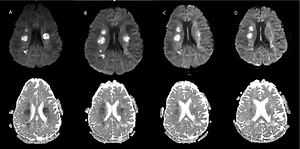

SARS-CoV-2 infection activating a novel variant of the NOTCH3 gene and subsequently causing development of CADASIL

Zbigniew J. Król,

Małgorzata Dorobek,

Maciej Dąbrowski,

Justyna Zielińska-Turek,

Bartosz Mruk,

Jerzy Walecki,

Katarzyna Sklinda,

Robert Gil,

Agnieszka Pawlak,

Marzena Wojtaszewska,

Adrian Lejman,

Paula Dobosz,

Paweł Zawadzki,

Aneta Pawłowska,

Michał Szczepaniak,

Dorota Król,

Artur Zaczyński,

Waldemar Wierzba

Arch Med Sci 2023;19(6):1781-1794